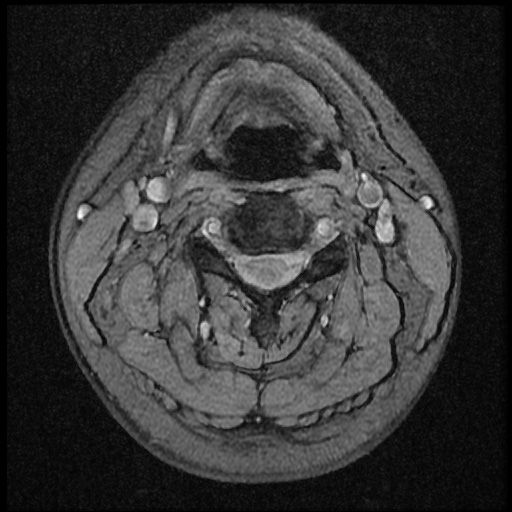

이 MRI 사진은 21년도 사고 당시 찍은 MRI 사진 입니다. 확인 부탁드립니다~

전체 mri를 다 봐여겠지만 보여주신 mri 컷에서는 의미있는 경추 디스크탈출이 보이지 않습니다.